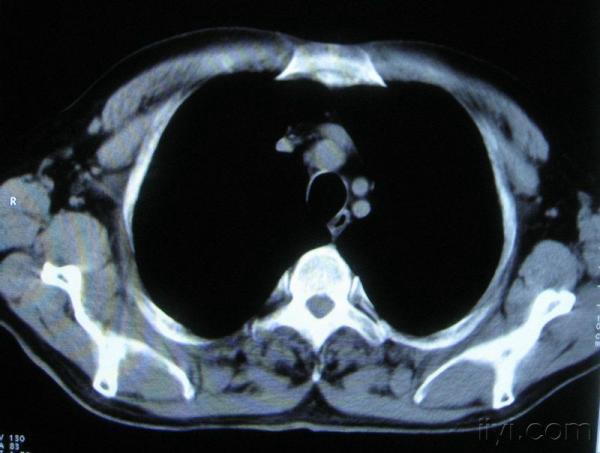

你指那个肯定是淋巴结,中央系坏死,这很常见,特别在双侧腹股沟会经常看到。这个双侧腋窝及纵隔见多发小淋巴结征。

根据位置考虑应该是淋巴结,密度不均,是因为肿大的淋巴结中心液化坏死